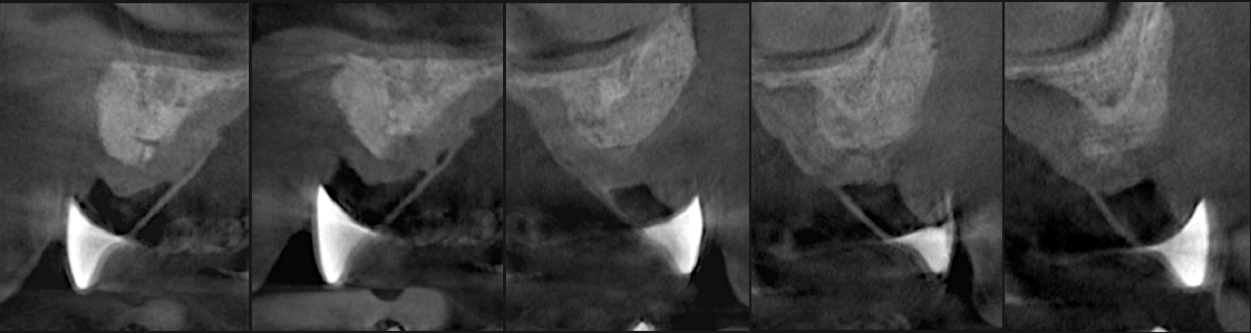

TREATMENT OF EXPOSED IMPLANT SURFACES

Bone regeneration over exposed implant surfaces is a novel application of the S.M.A.R.T. technique. Bone may be absent for a variety of reasons, usually related to placement or bone remodeling.

As bone loss advances, implants may need to be removed and treatment started all over again. Traditional techniques have shown limited success in regenerating bone over implants. The S.M.A.R.T. technique has been successful in treating exposed implant surfaces with up to 3 year follow up. It provides a simplified, predictable and cost-effective alternative, with less patient discomfort.